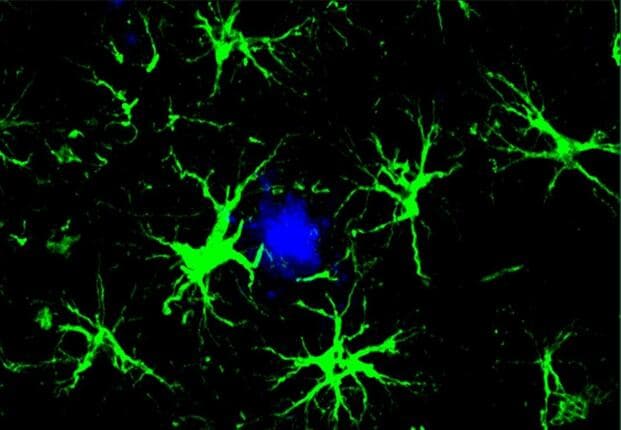

The APOE gene has three main variants: APOE2, APOE3, and APOE4. Each variant codes for a slightly different version of the APOE protein, which plays a crucial role in transporting fat molecules through the bloodstream. However, the APOE protein also interacts closely with amyloid-beta, a protein that aggregates into plaques, destroying neuronal connections and triggering inflammation in the brain.

Previous research suggested that APOE2 was protective, while APOE4 increased Alzheimer's risk. APOE3 was thought to be neutral. However, a new study analyzing data from 450,000 individuals revealed that APOE3 also increases Alzheimer's risk, albeit to a lesser extent than APOE4. Carrying two copies of APOE2 makes individuals almost immune to developing Alzheimer's, while APOE4 significantly impairs fat processing in glial cells, increases cell death, and hampers synaptic plasticity.